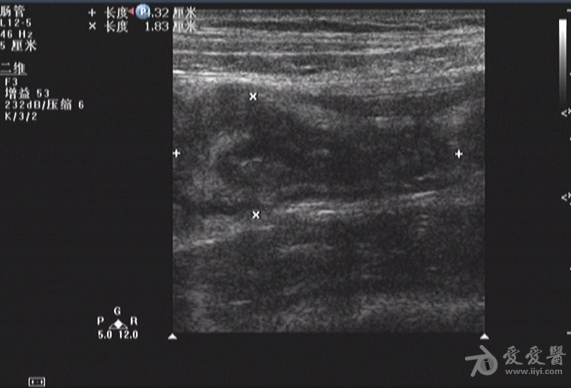

自认为---回盲瓣回声---zengerya - 超声医学讨论版 - 爱爱医医学论坛

图片尺寸601x416